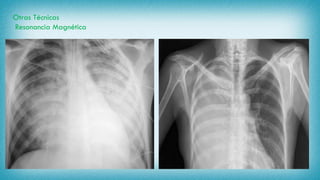

Radiografía de Tórax

Tomografía Axial Computarizada

Otras Técnicas

Resonancia Magnética